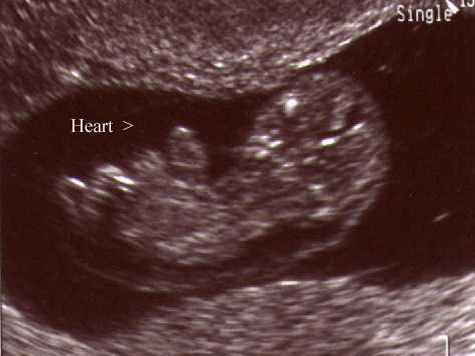

Диагностика. Наличие полной формы дизрупции порока развития передних стенок грудной клетки и брюшной полости, которая сопровождается пятью признаками, описанными J.R. Cantrell et al., является классической формой пентады и может быть выявлена при ультразвуковом исследовании начиная с середины второго триместра. Обнаружение сокращающегося вне пределов грудной клетки сердца в сочетании с омфалоцеле позволяет установить диагноз пентады. Для исключения хромосомных аномалий рекомендуется проведение кариотипирования. Вследствие компрессии органов как грудной клетки, так и брюшной полости могут возникать асцит и гидроторакс.

В одной из столичных женских консультаций специалисты, наблюдавшие беременность одной из пациенток, не заметили серьезной патологии. И только когда женщина, собрав сумки в роддом, решила на всякий случай сделать УЗИ в коммерческом центре, несчастной открыли глаза. Сердце ребенка бьется за пределами грудной клетки. Снаружи также находятся печень и кишечник.

Пентада Кантрелла — уникальное сердечное заболевание, оно встречается у пяти детей из миллиона, причем чаще всего в легкой форме. При этой патологии сердце смещено в сторону брюшной полости. Впервые ее описал в 1958 году доктор Кантрелла, указав 5 основных признаков заболевания. С тех пор она так и называется — пентада Кантрелла. В действительности довольно редко рождаются дети со всеми пятью признаками синдрома. Но в данном случае российским врачам впервые предстояло столкнуться с “полным набором”.